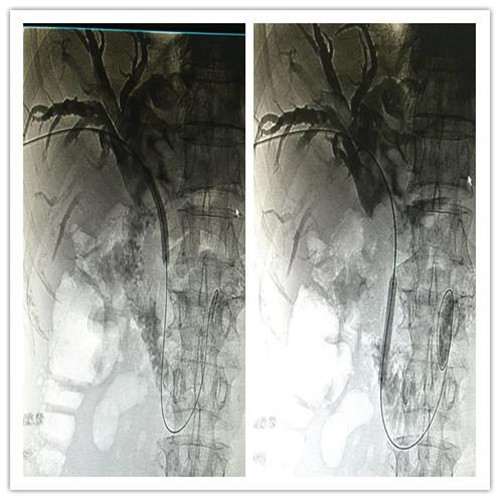

4月4日,MILAN.COM介入科成功为一位78岁高龄,胆系高位梗阻性黄疸、胆管占位病变的患者紧急成功实施了PTCD(经皮肝穿胆管引流术)。

患者全身皮肤金黄瘙痒难忍,在B超定位下行肝内胆管引流术、术后因引流不畅拔管;在胃镜下逆行ERCP胆管支架植入术,经过术者反复操作,但导丝无法通过病变段。看到患者痛苦不堪,家属迫切治疗的场面,介入科李建国主任现场会诊提出为患者在介入下行PTCD治疗的意见。术前经过讨论制定多套严密方案,与患者及家属多方沟通达成介入手术共识;术中精准定位穿刺选择不同的导丝、导管多角度旋转闭塞原地不动,时间一分一分过去......在医护人员努力下,闭塞的胆道开通了,再经球囊分段扩张病变狭窄段,内外引流管放置顺利300余毫升的黑褐色胆汁流出......

在护理人员精心的配合下,手术历时30余分钟圆满成功,彻底解决了患者梗阻性黄疸引发的皮肤黄染,保护了肝功能。

顺行开通高位胆管梗阻性黄胆经皮肝穿胆管引流术优势明显